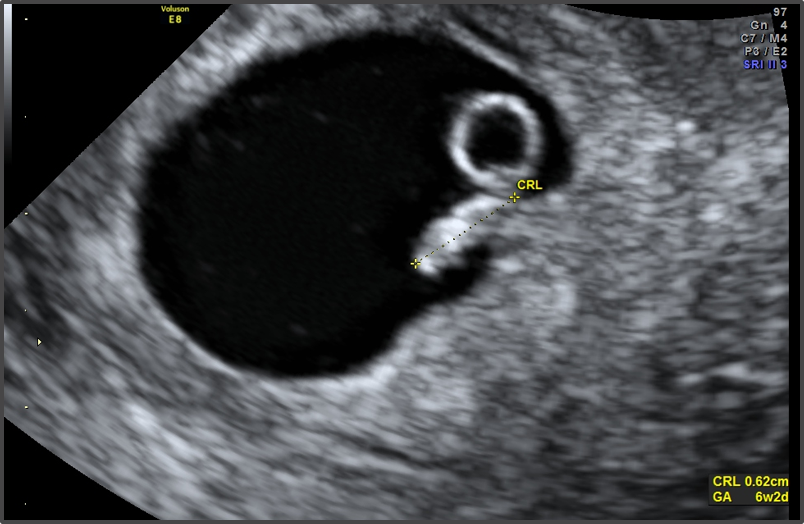

Какво представлява изображението от ехографията на 5-седмична и 2-дневна бременност?

Кога обикновено може да се види ембрионът на ултразвукова снимка?